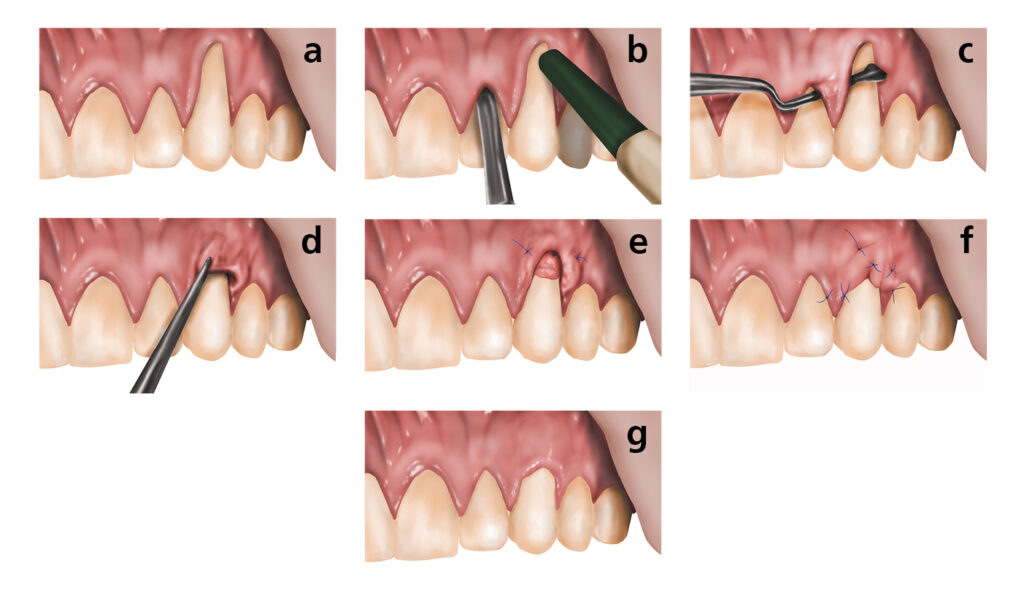

Recession exposes the tooth root, which has no enamel protection. This leads to sensitivity, especially to cold or sweet foods, and significantly increases the risk of root decay. Receded gum tissue does not grow back on its own — but it can be restored with a gum grafting procedure performed by a periodontist.

Early-stage gum disease (gingivitis) can often be managed with a professional cleaning and improved home care. More advanced disease may require scaling and root planing, surgical pocket reduction, or regenerative procedures. The sooner you come in, the more options are available — and the more of your natural teeth we can preserve.